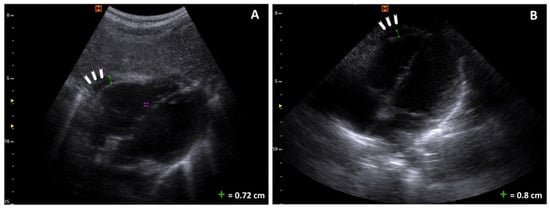

Upon admission to our PED, a complete POCUS was performed, which showed bilateral pleural effusion, mild pericardial effusion, and ascites without other signs of pulmonary parenchymal or cardiac involvement (Figure 1, Figure 2 and Figure 3). Bedside focused cardiac ultrasonography (FoCUS) allowed us to exclude systolic dysfunction or cardiac tamponade.

Figure 2. Pericardic effusion: (A) a four-chamber subcostal scan with an effusion of maximum thickness of 0.78 cm (arrowheads); the purple cursor is a measurement typo; (B) a four-chamber apical scan with an effusion of maximum thickness of 0.8 cm (arrowheads).